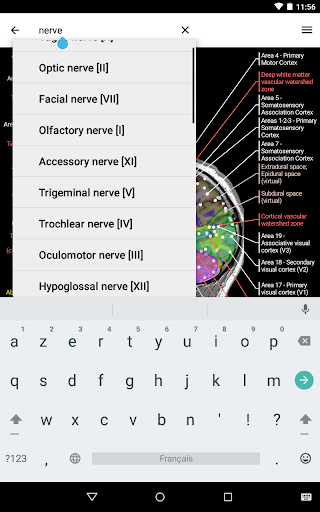

e-Anatomy tiene más de 26 000 imágenes que contienen series de imágenes en vistas axiales, coronales y sagitales, así como radiografías, angiografías, imágenes de disección, gráficos anatómicos e ilustraciones. Todas las imágenes médicas fueron etiquetadas cuidadosamente, más de 967 000 etiquetas disponibles en 12 idiomas, incluida la Terminologia Anatomica latina.

- Localice fácilmente las estructuras anatómicas gracias a la búsqueda de índice

*Encuentre sus partes anatómicas más fácilmente gracias a la nueva función de búsqueda, más intuitiva y poderosa.